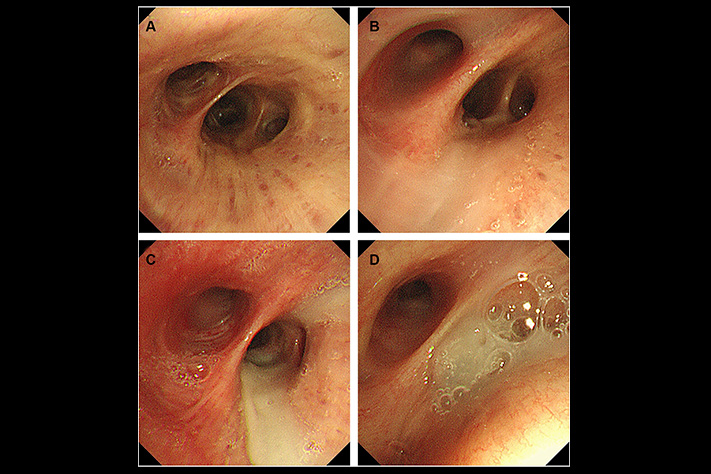

What they found: In every single patient's airways, there was a dense layer of mucus at the very bottom-below the fresh mucus, below where any treatment could reach.

The layer had been there for months. Sometimes over a year.

The cilia-those tiny hairs that sweep mucus out-were completely buried under it. Non-functional.

The researchers tested standard treatments on this bottom layer.

Nothing worked. Not Mucinex. Not saline nebulizers. Not NAC. Not any expectorant or supplement.

The molecular structure was different. Denser. Surface treatments couldn't break it down.